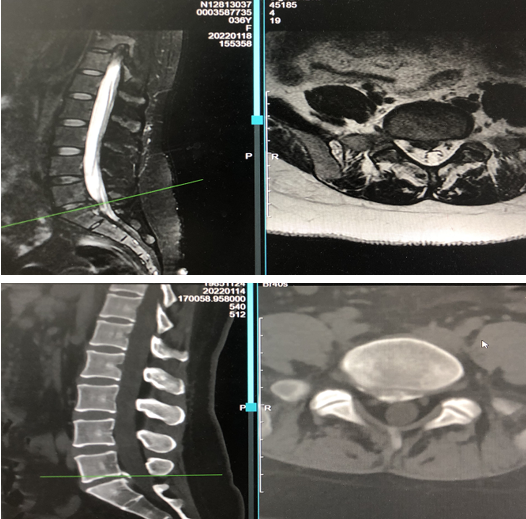

Luckily, she was diagnosed by the team of Dr. Fu Qiang. On admission, the patient was found to have a fibrosarcoma with possible systemic metastasis, poor condition, a large disc prolapse between L5-S1 of his lumbar spine combined with significant calcification, and severe neural adhesions in the lumbar spinal canal.

Through a 5 mm incision, the surgical team precisely punctured the herniated disc, established a working channel and inserted the spinal endoscope. Under a 50x magnified view, the team found severe adhesions around the nerve tissue in the lumbar spinal canal and a large prolapsed disc ventral to the nerve root with calcification. They placed a pre-connected laser fiber through the working channel to excite the spine-specific laser and safely and effectively removed the adhesions around the herniated disc nerve using laser separation, ablation and vaporization functions. The surgery took only 23 minutes, with only 5 ml of intraoperative bleeding.